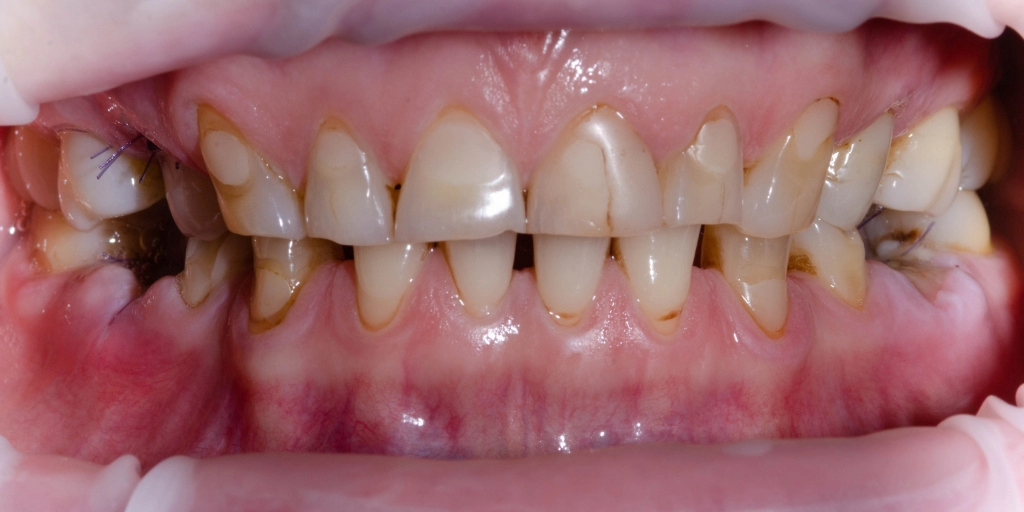

Женщина. 52 года.

Обратилась с жалобами на разрушение зубов 3.6, 4.6, дефекты и дисколорит ранее наложенных пломб. В анамнезе врожденная адентия 1.5, 2.5, 3.5, 4.5